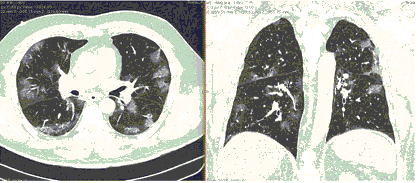

КТ имеет высокую чувствительность в выявлении изменений в легких, характерных для COVID-19. Применение КТ целесообразно для первичной оценки состояния ОГК у пациентов с тяжелыми прогрессирующими формами заболевания, а также для дифференциальной диагностики выявленных изменений и оценки динамики процесса. КТ позволяет выявить характерные изменения в легких у пациентов с COVID-19 еще до появления положительных лабораторных тестов на инфекцию с помощью МАНК. В то же время, КТ выявляет изменения легких у значительного числа пациентов с бессимптомной и легкой формами заболевания, которым не требуется госпитализация. Результаты КТ в этих случаях не влияют на тактику лечения и прогноз заболевания при наличии лабораторного подтверждения COVID-19. Поэтому массовое применение КТ для скрининга асимптомных и легких форм болезни не рекомендуется.

- Изменения при КТ (рентгенографии), типичные для вирусного поражения (объем поражения минимальный или средний; КТ 1-2)

- Изменения в легких при КТ (рентгенографии), типичные для вирусного поражения (объем поражения значительный или субтотальный; КТ 3-4)

- Изменения в легких при КТ (рентгенографии), типичные для вирусного поражения критической степени (объем поражения значительный или субтотальный; КТ 4) или картина ОРДС.